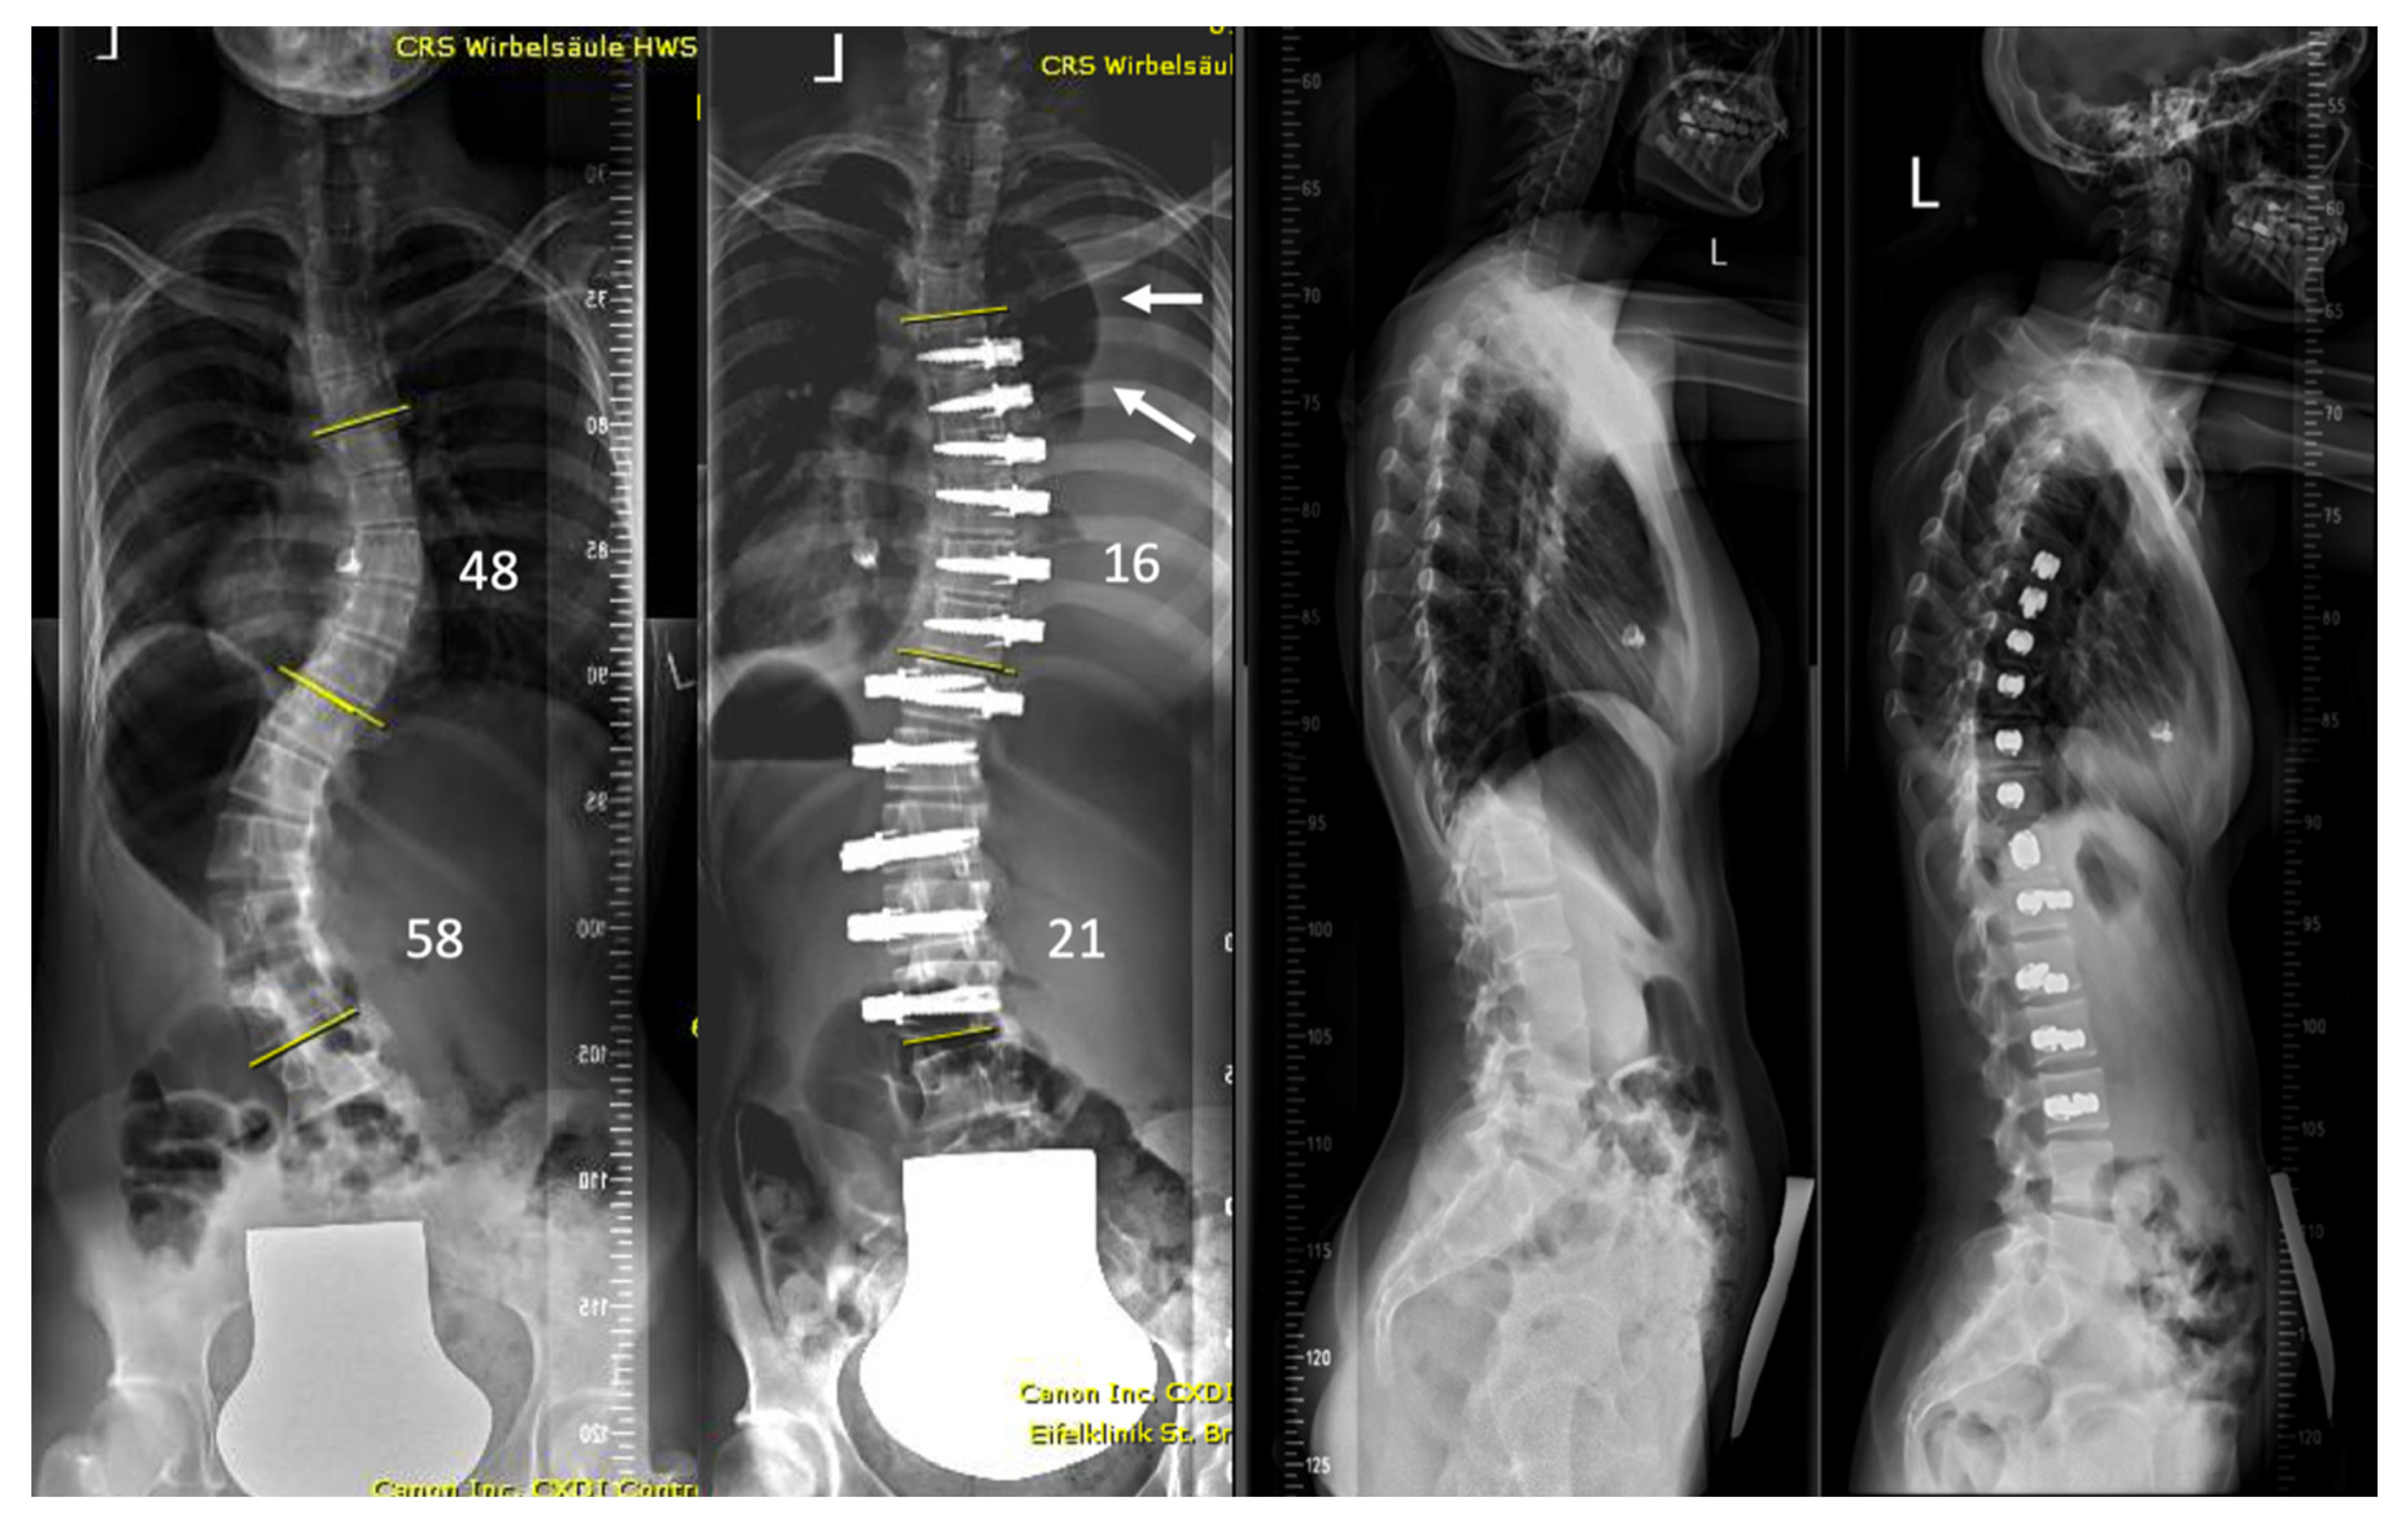

Examples of the X-rays of the two asymptomatic patients are shown in Figure 2 and Figure 3. Figure 4 shows the evolution of patient n. 6, who presented a chylothorax.

Figure 2.

The patient (n. 8 in the series) presented with a lumbar curve that measured 41° but resulted in a severe coronal imbalance and the patient suffered from daily pain. Surgery was able to almost completely correct her deformity. Pleural effusion on the left was diagnosed on routine post-operative radiographs with a vanished lateral recess (white arrow; ** shows a visible right lateral recess for comparison).

Figure 3.

17-year-old but very small patient (34 kg) with mild form of Di-George syndrome, which is known to present with vessel anomalies. Post-operative recovery was uneventful with no symptoms of fatigue or shortness of breath. Severe pleural effusion was noticed on first erect postoperative spine radiograph (arrows).